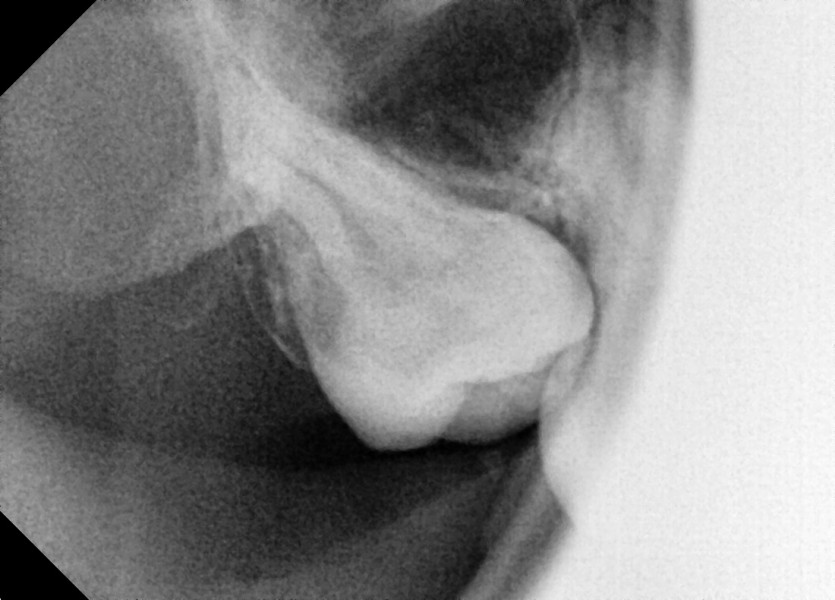

#18 사랑니 발치

구강 외과 전문의가 당일 발치했습니다.